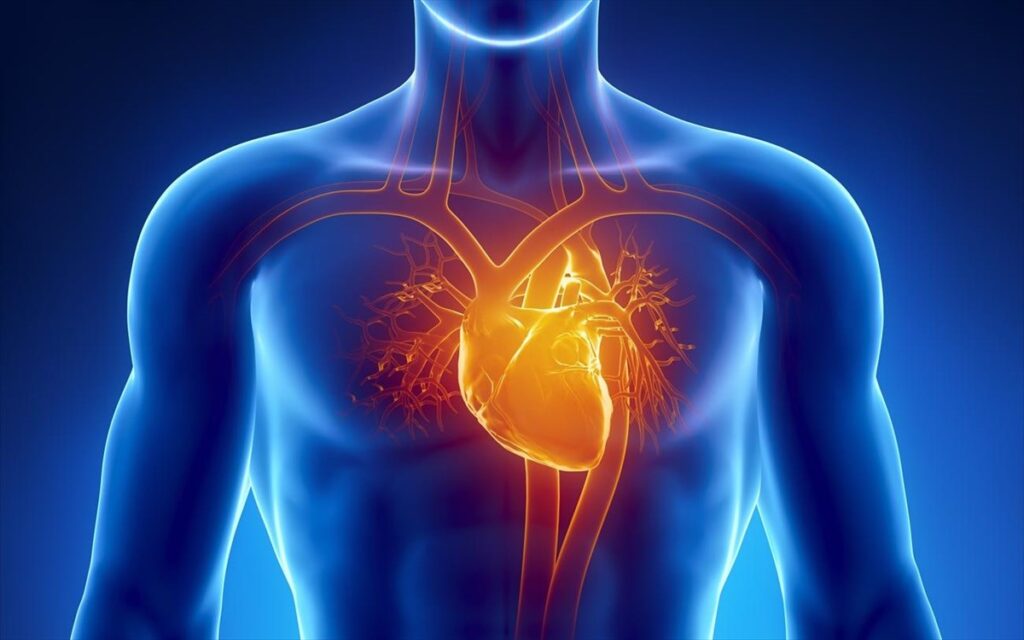

Η καρδιακή ανεπάρκεια είναι μια χρόνια και προοδευτική πάθηση, κατά την οποία η καρδιά αδυνατεί να αντλήσει και να στείλει αρκετό αίμα στο σώμα, ώστε να καλύψει τις μεταβολικές του ανάγκες.

Η στεφανιαία νόσος είναι μια χρόνια πάθηση που επηρεάζει τις στεφανιαίες αρτηρίες, δηλαδή τα αγγεία που τροφοδοτούν την καρδιά με αίμα και οξυγόνο.